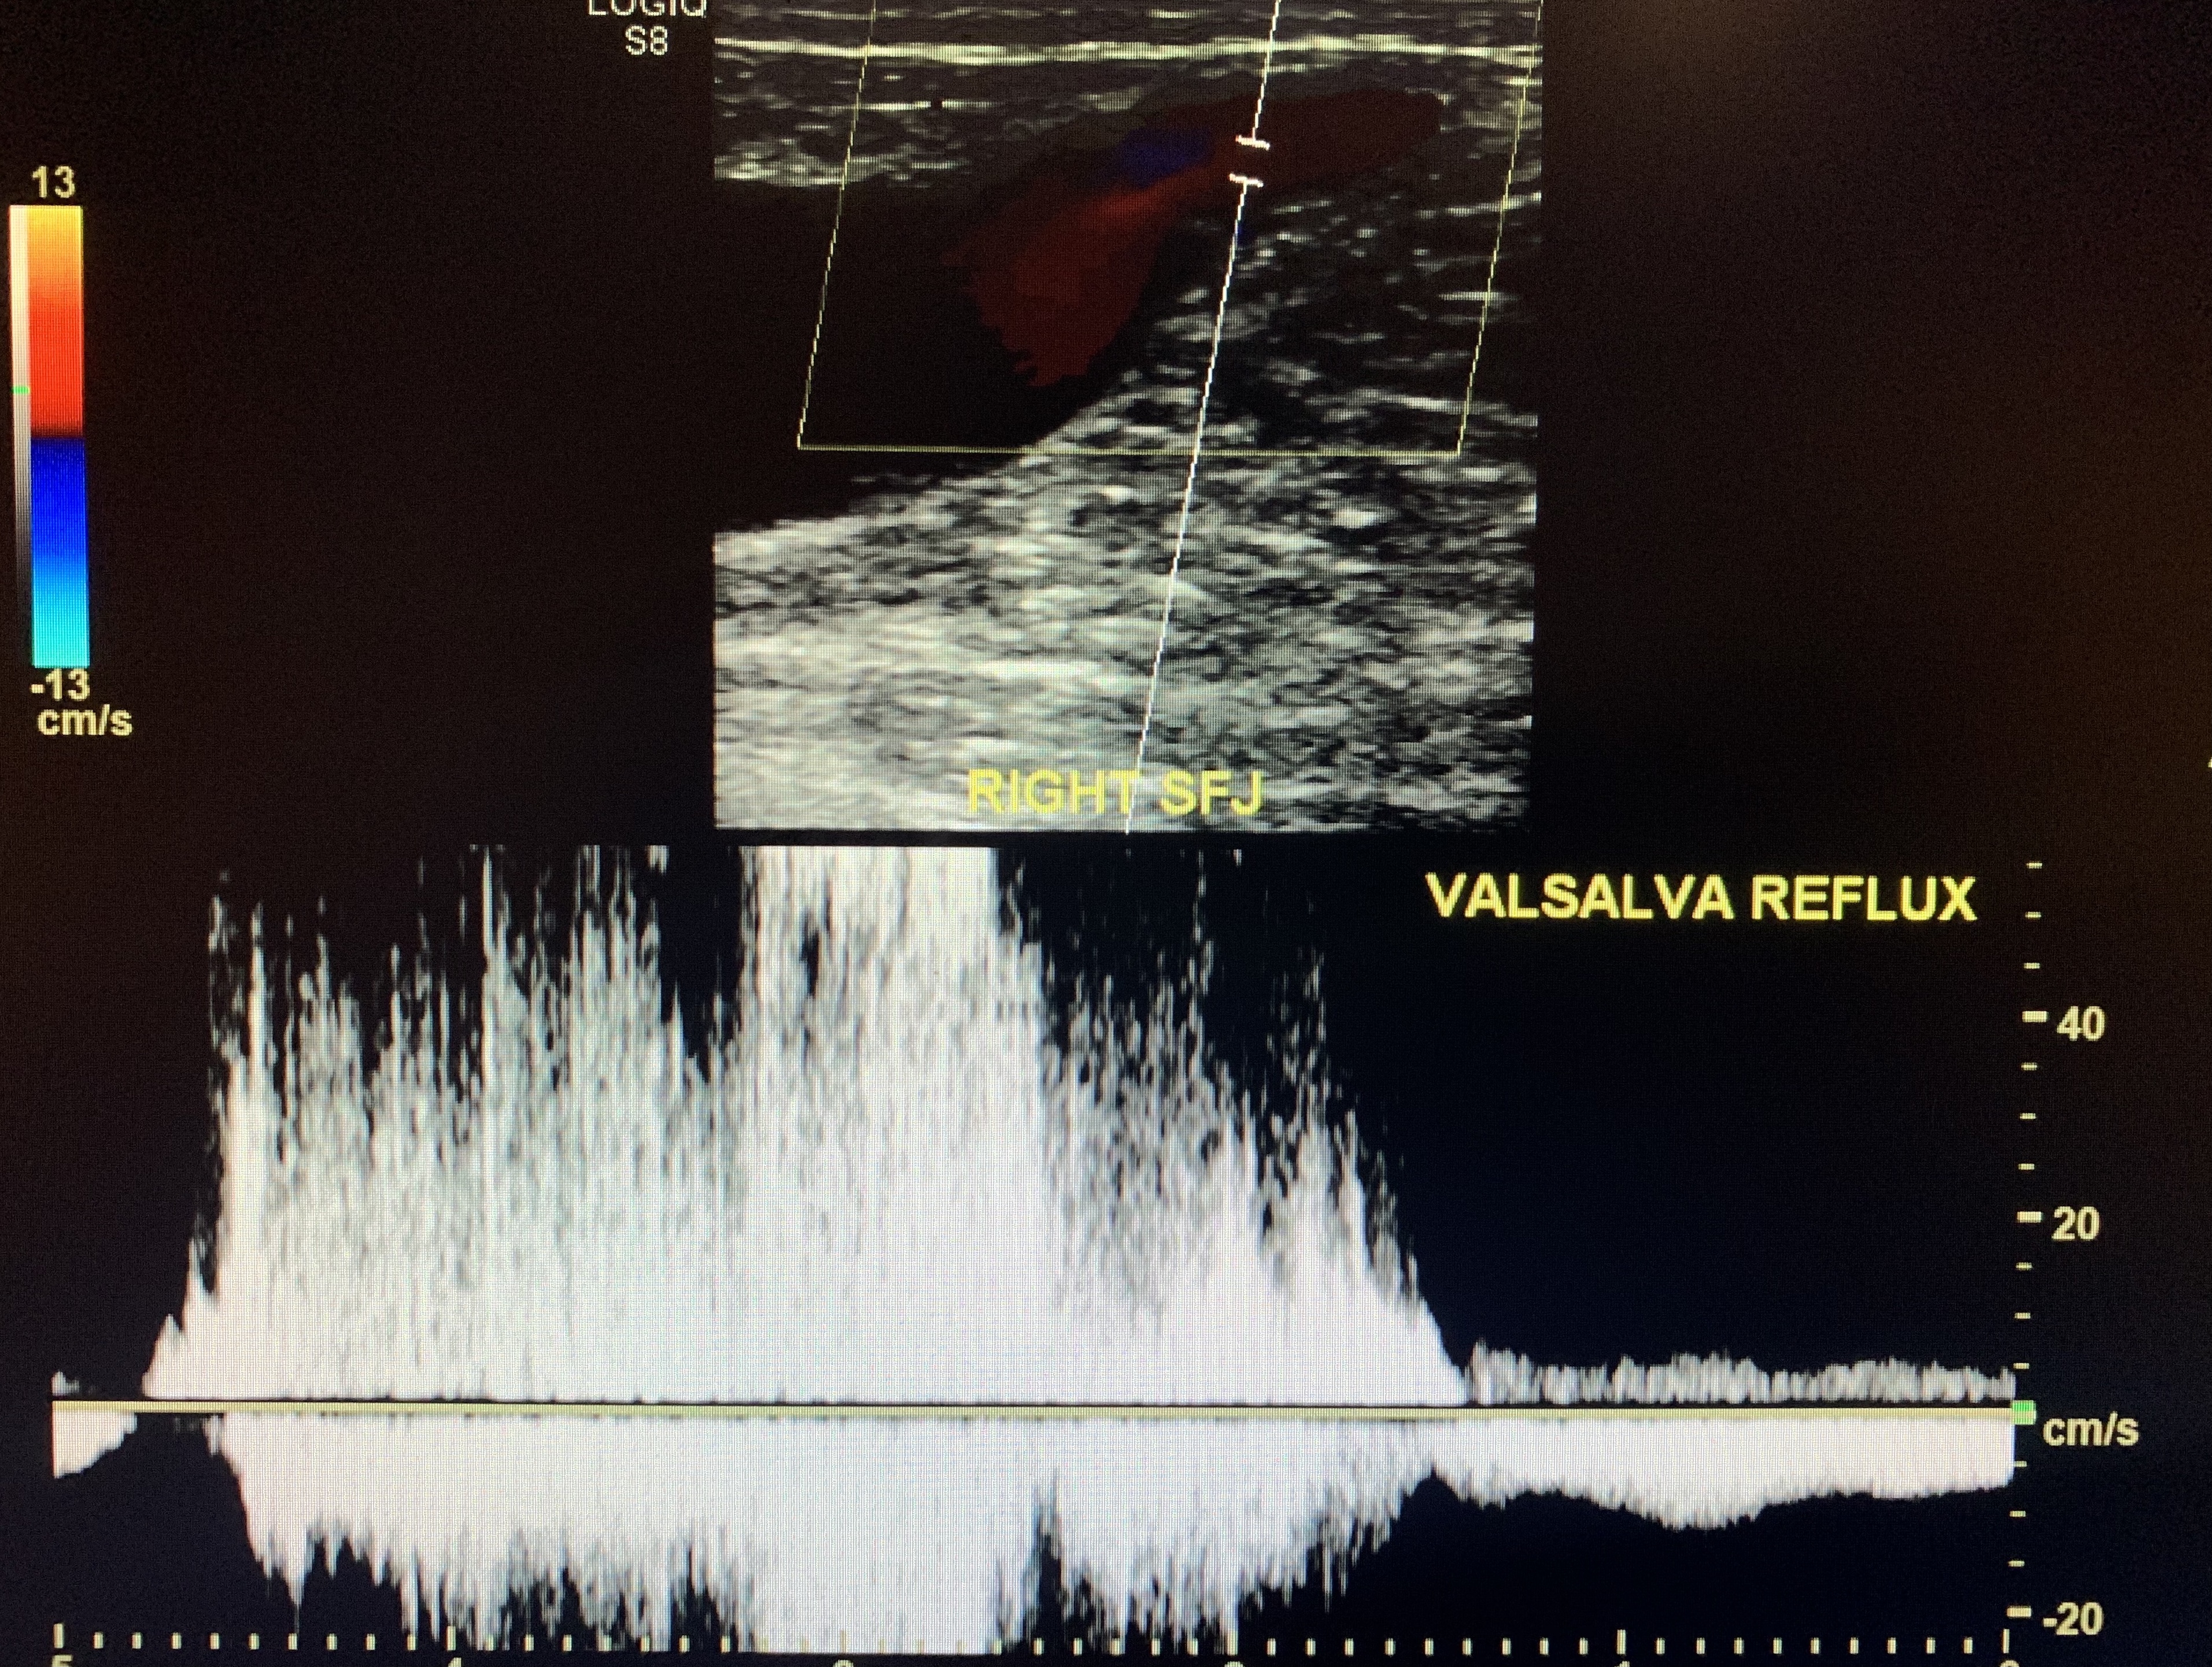

Sapheno-Femoral Junction

Ask the patient to perform the valsalva technique by having them bare down and strain.

This should elicit retrograde flow if the SFJ is incompetent. Positive reflux is >0.5 seconds for all superficial veins.

This patient demonstrates a considerably severe reflux in the SFJ (up to 4 seconds) performed w/ valsalva.